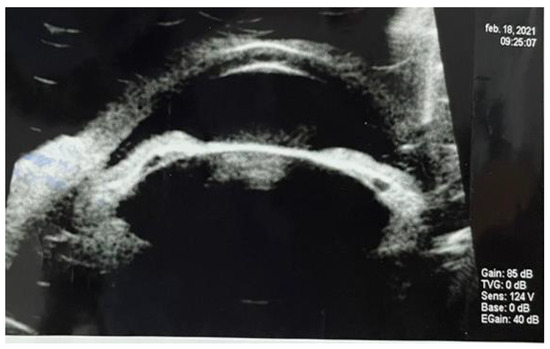

Ultrabiomicroscopy (UBM) confirmed posterior irido- lenticular synechiae on 360⁰ and thickening of the ciliary body (Figure 1). Ocular ultrasound exam revealed total retinal detachment, multiple fine vitreous echoes suggestive for vitritis, homogeneous thickening of the choroid and a 3mm diameter hyperechogenic mass invading sclera (Figure 2). A differential diagnosis between an extrascleral extension of an endophthalmitis and a possible intraocular tumor with scleral penetration was considered.

Figure 1.

Ultrabiomicroscopy: circumferentially posterior synechiae and ciliary body thickening.